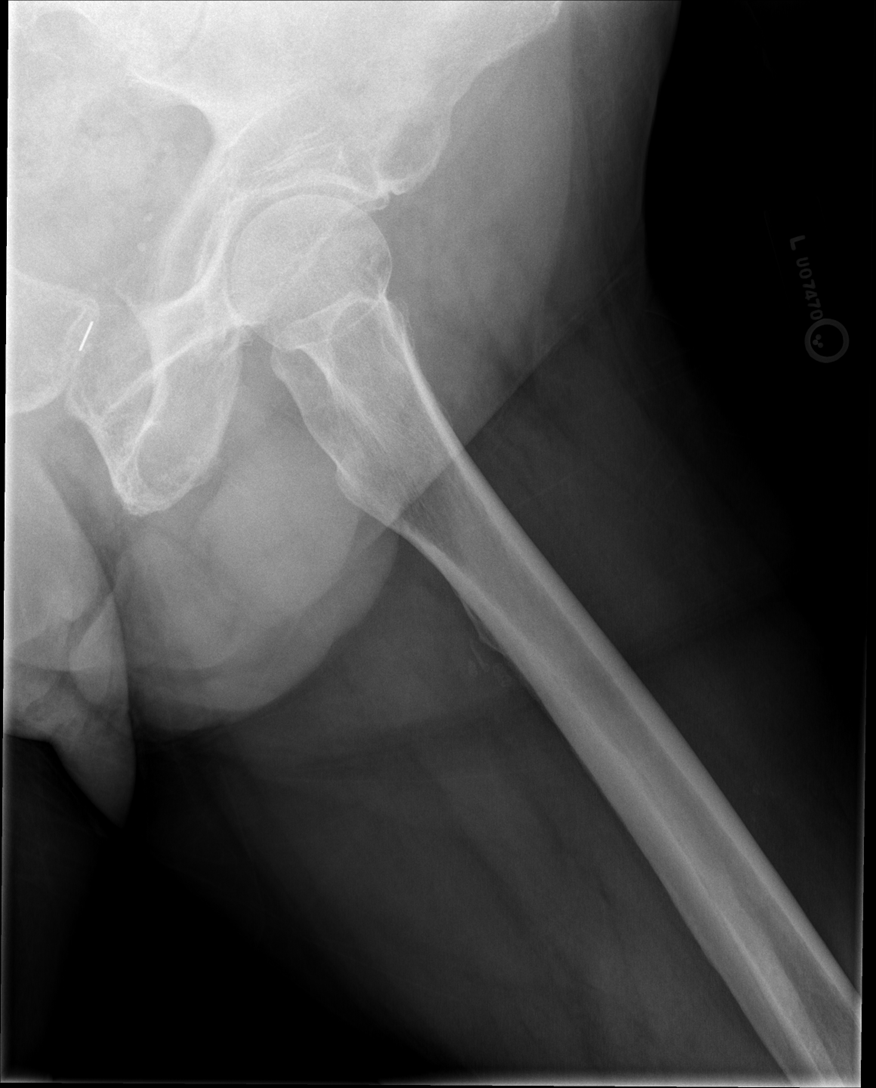

Lateral Femur

•Evidence of proper collimation and the presence of a side marker placed clear of the anatomy of interest

•Most of the femur and the joint nearest to the pathologic condition or site of injury (a second projection of the other joint is recommended)

•Any orthopedic appliance in its entirety

•Bony trabecular detail and surrounding soft tissues

•

With the hip included (proximal)

•Opposite thigh not over proximal femur and hip joint

•Greater trochanter superimposed over distal femoral neck

•Lesser trochanter visible on medial aspect of proximal femur

Under-rotated, sticking out laterally REPEAT, place marker bottom of light field

Can not see e lesser trochanter, can not see the greater trochanter sticking out laterally, OVER ROTATED can not see lesser

Under rotated, prominent lesser trochanter, femur is not parallel, not fully lateral, wide collimation

REPEAT under rotation